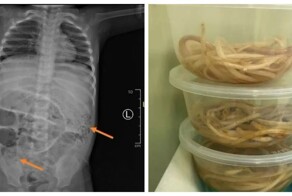

- Напоминание не пить сырую воду: кадры извлечения из тела пациента гигантских червей